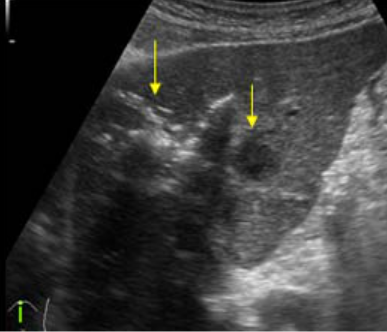

US finding

- (초기) 경계가 분명한 원형, 타원형 종괴로 내부에코는 저에코이다.

- (후기) 진행될수록 무에코로 변한다.

- location: 간표면 근처

amoebic abscess 2) 기생충성이 아닌 간낭종 (non-parasitic )